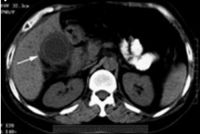

- 辅助检查:白细胞计数常增高,中性白细胞也增高。如总数超过每立方毫米20000时,应考虑总胆管内感染严重或有积脓,甚至胆囊有坏死或穿孔的可能。B超检查示胆囊增大,壁厚>3.5mm,内有强光团伴声影.静脉胆道造影胆囊不显影.CT或MR显示胆囊结石。